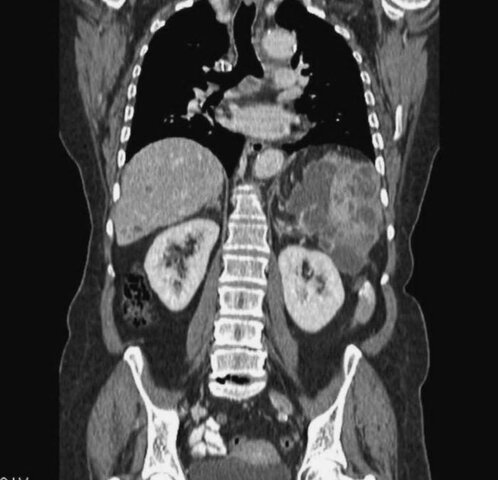

• Tomografía Computarizada

Tomografía Computarizada

En este año el señor Godfrey houndsfield presenta su escáner y su técnica de la TAC, de gran transcendencia en la historia de la radiología. Órganos nunca antes vistos radiológicamente se expusieron con gran calidad ante nuestros ojos.